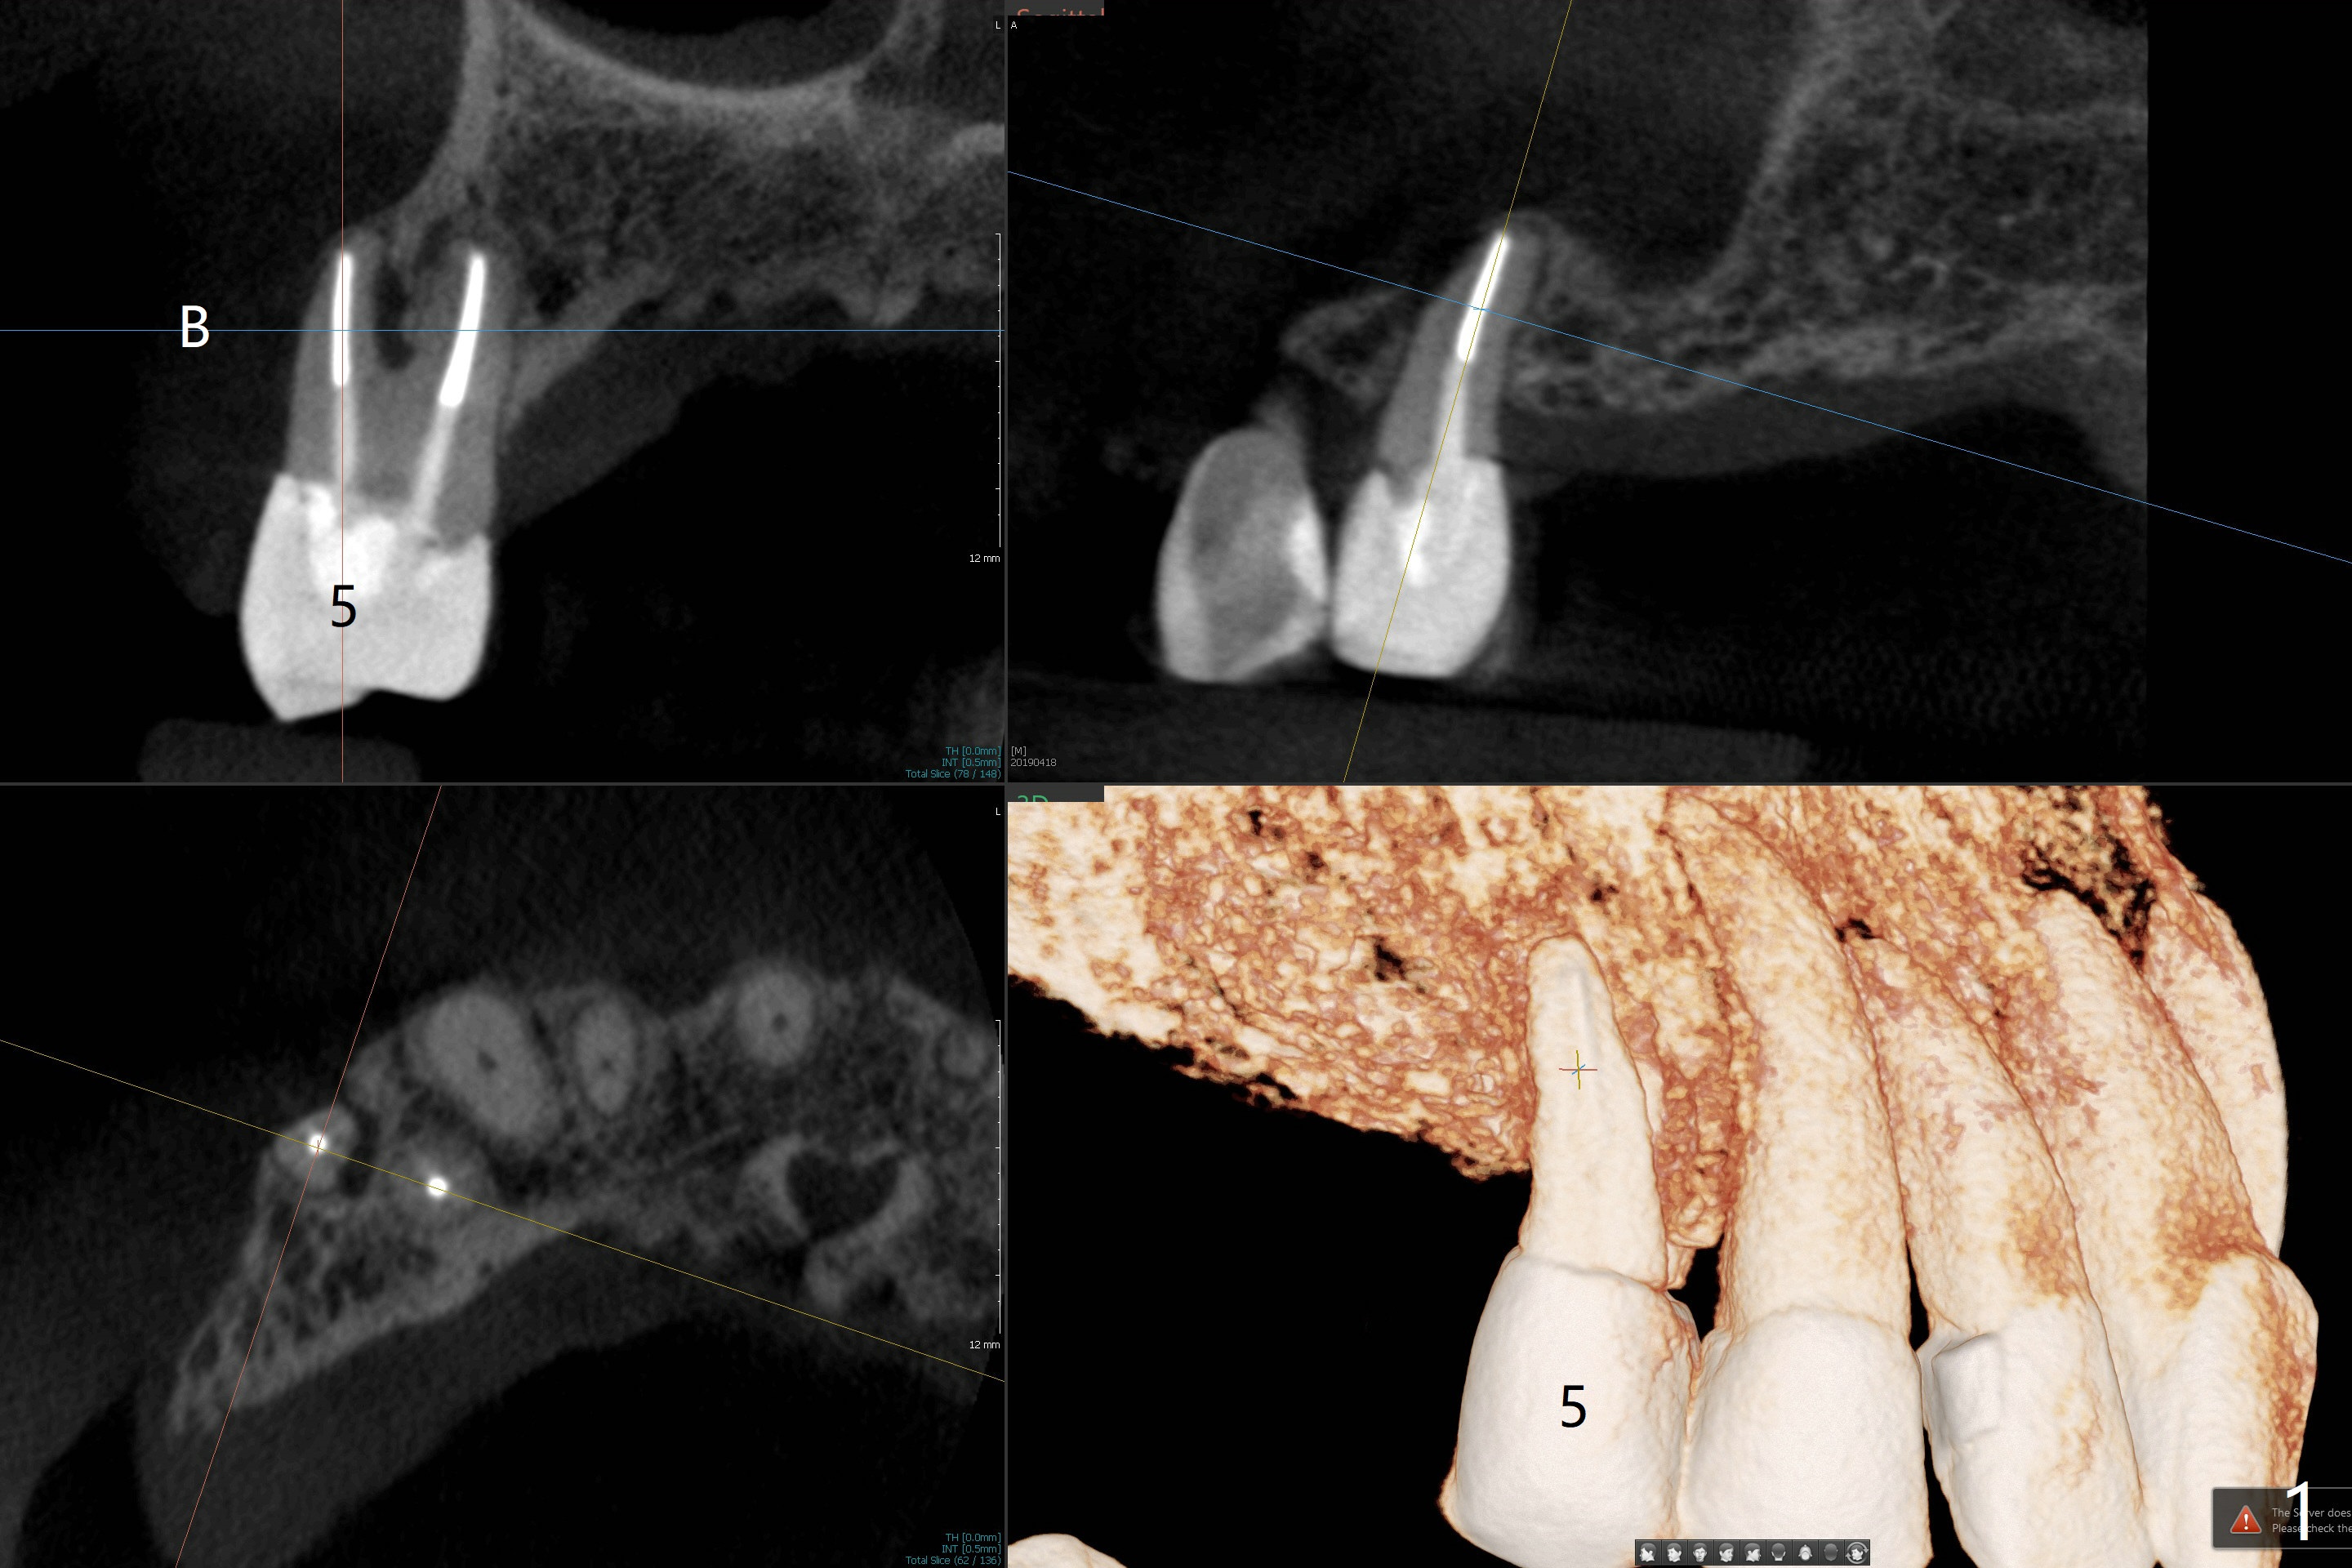

A 71-year-old woman with RPDs develops a fistula buccal to the tooth #5 (Fig.1). The buccal root seems to be fractured as indicated by arrowheads in Fig.2,3 (coronal and sagittal sections). The diagnosis of the fracture is confirmed by the abrupt change in density shown in Profile and the coronal section in Fig.4. Three-dimensional image demonstrates bone over the root surface of the teeth 6 and 8 (Fig.5 *), as compared to no bone over the the buccal root of the tooth #5. Due to financial constraint, the buccala root amputation is proposed as a treatment option. Is it viable?